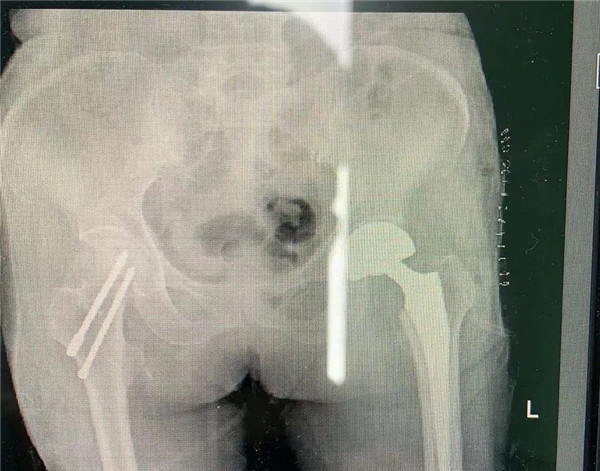

手術(shù)由危立軍副院長(zhǎng)主刀,用最少的時(shí)間完成人工關(guān)節(jié)置換,從劃刀到假體安裝好僅僅10分鐘。術(shù)后王老太太一天天好轉(zhuǎn)起來,現(xiàn)已下地康復(fù)行走,臉上洋溢開心的笑容。